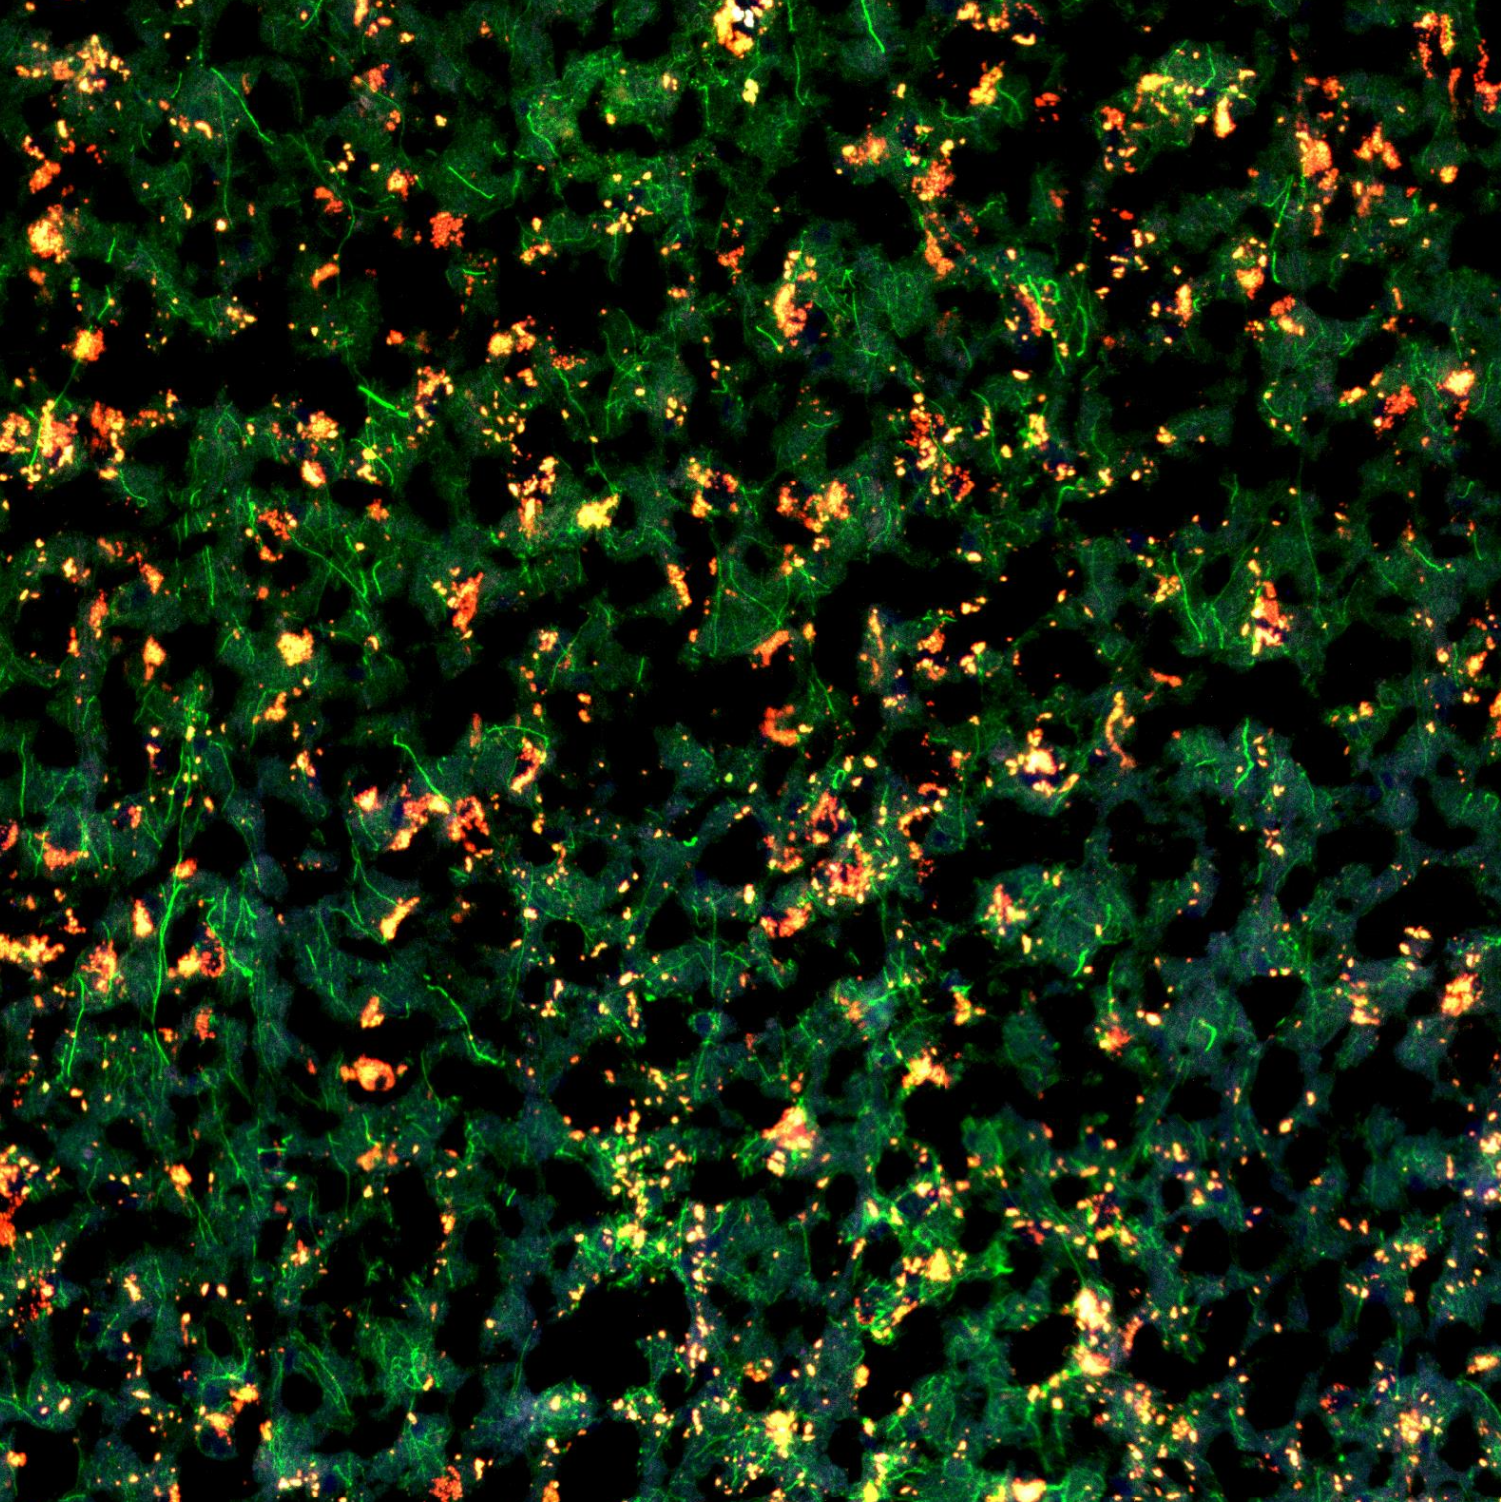

Adding morphology markers

2h 15m

NOTE – Morphology marker preparation will vary and should be empirically tested. Here we used unconjugated antibodies and thus modified the NanoString GeoMx protocol accordingly

Prepare morphology marker solution as per the table below

ABC

ReagentDilutionVolume

Buffer W-(n) x 220 µl

GFAP1:1000(n) x 0.22 µl

P2RY121:100(n) x 2.2 µl

Morphology marker solution (n) indicates number of slides

During incubation, prepare secondary antibody mixture as per the table below

AF4881:1000(n) x 0.22 µl

AF6471:500(n) x 0.44 µl

During incubation, prepare nuclear stain as per the table below

SYTO831:1000(n) x 0.22 µl